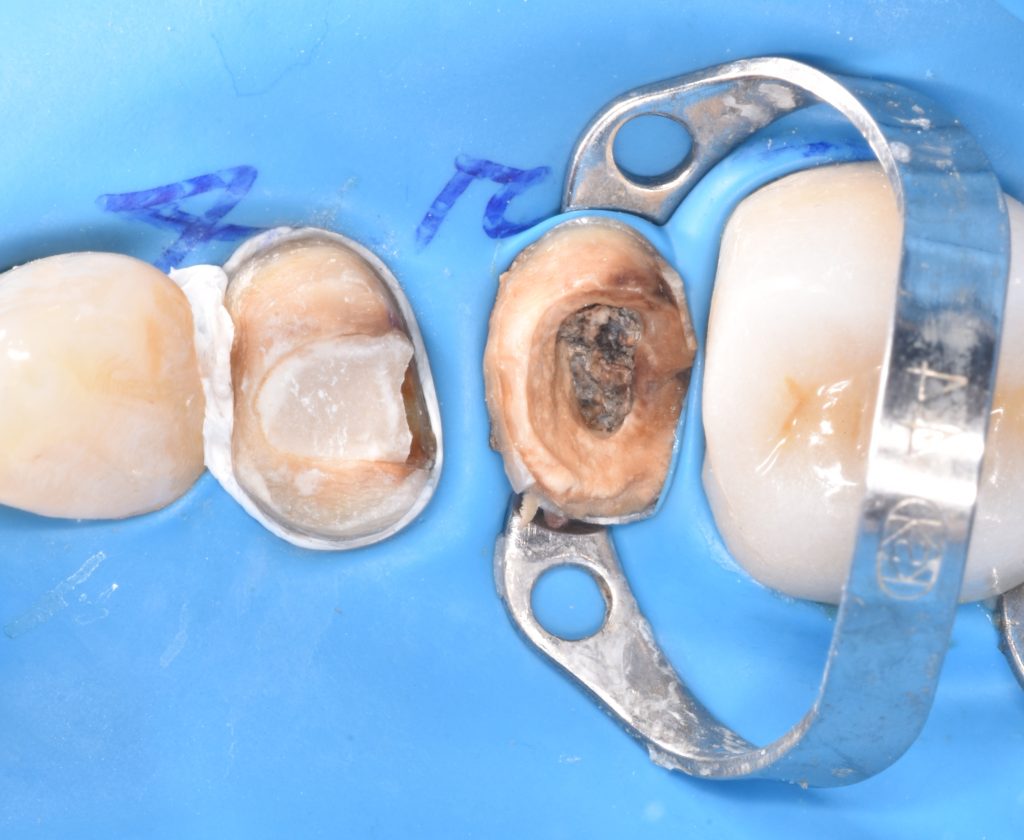

Upper right first and second premolars

Were badly decayed

Rubber dam isolation is mandatory in such cases

Caries removal with aid of caries detector dye

Deep margin elevation using circumferencial Copper bands

Elevation by snow plow technique n